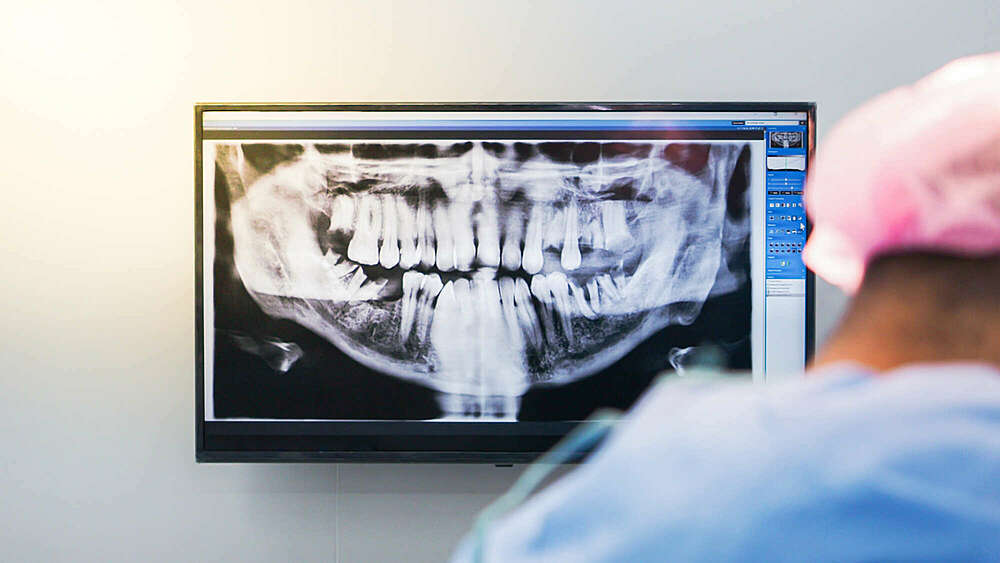

La radio panoramique

L'image panoramique est une pratique orthodontique standard, réalisée pour tous les patients en cours de développement dentaire ou qui entament un traitement. Le Dr Topolanski, votre orthodontiste à Paris 17, préconise la réalisation d'une imagerie panoramique autour de 8-9 ans pour obtenir une vision complète de la dentition existante et en progression.

Cette radiographie permet d'analyser :

- la trajectoire de l'éruption des dents,

- le décompte des dents (certaines peuvent être absentes ou en surplus),

- leur forme, taille et niveau de développement (âge dentaire – retard ou avance),

- l'existence de pathologies (kystes, hypercalcification, résorption, usure, etc.).

L'imagerie panoramique est réalisée au début du traitement, à mi-parcours pour vérifier la position des dents, l'inclinaison des racines et la présence d'usure radiculaire (résorption), etc. et à la fin du traitement. Elle est également réalisée après la fin du traitement à des intervalles de quelques années pour surveiller l'évolution des dents de sagesse.

Pendant la phase de dentition mixte (~6 à 12 ans), elle permet au Dr Topolanski, votre orthodontiste à Paris, de détecter la présence de problèmes d'éruption et d'autres anomalies et lui permet de faire des recommandations qui peuvent minimiser certains problèmes. La radio panoramique est un outil essentiel pour la prévention et l'interception en orthodontie.